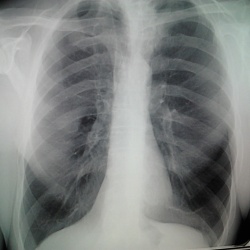

Мужчина 1975 г.р.,проходит флг,в направлении от терапевта-левосторонняя пневмония?планирую отправить в ПТД,но хотелось б послушать ваши мнения по данным снимкам.Спасибо.